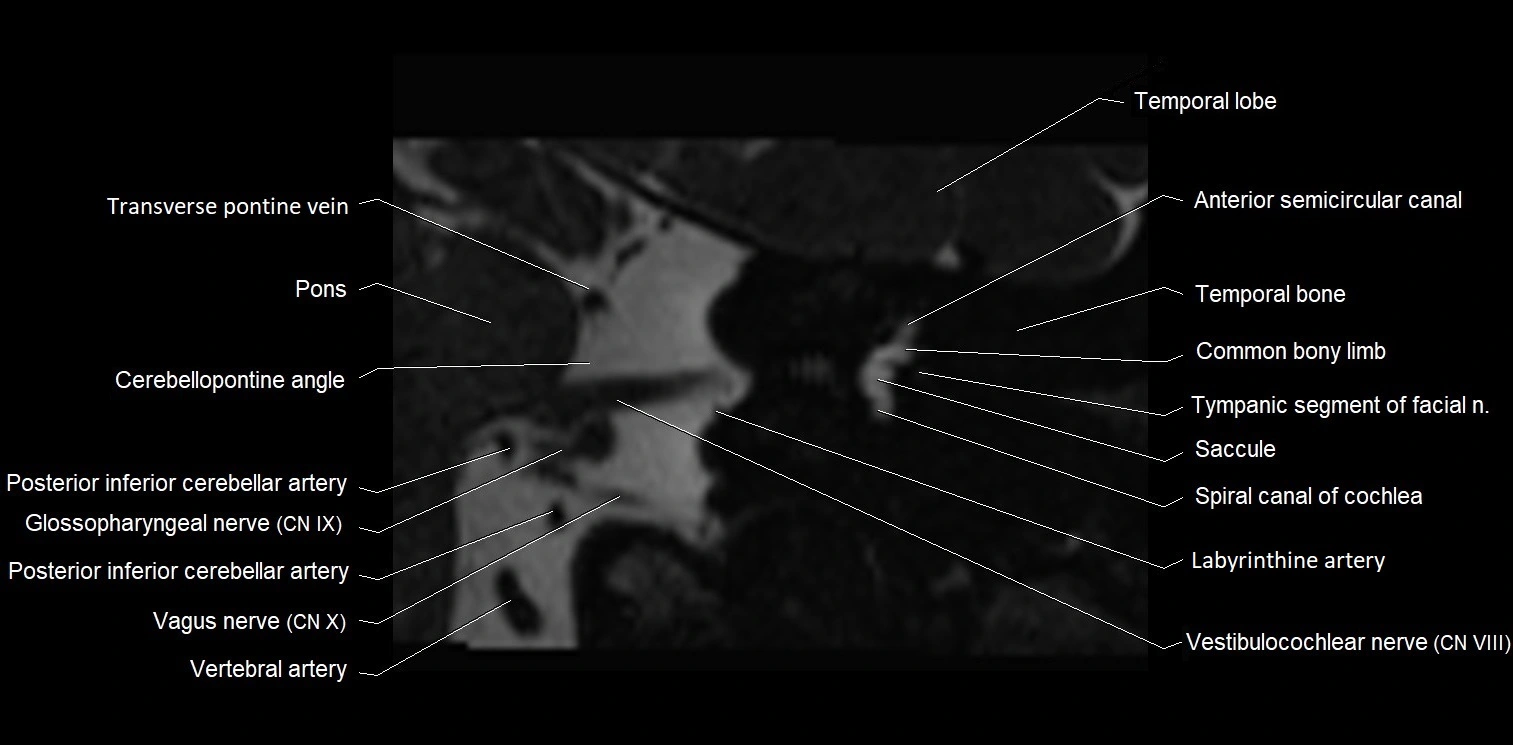

image